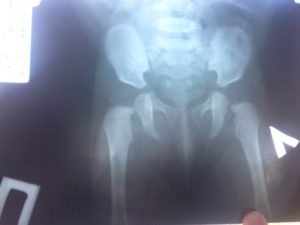

Если тазобедренный сустав имеет связанную с развитием ядра патологию, ее обнаружит УЗИ. Для ее выявления применяют и методы сонографического исследования. Часто может потребоваться и рентгенологическое исследование таза. Рентгеновский снимок для этого выполняется в прямой проекции.

Он дает возможность врачам получать максимально точную информацию о наличии или отсутствии патологии.

Патология ядра выявляется при помощи ультразвукового и сонографического исследования. Дополнительно проводится рентген поврежденных суставов таза. Для рентгеновского снимка выбирается прямая проекция, благодаря чему врачи могут получить более точную и подробную информацию о состоянии опорно-двигательного аппарата ребенка.